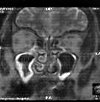

МРТ околоносовых пазух

МРТ околоносовых пазух. Высокоинформативный метод диагностики, основанный на явлении ядерного магнитного резонанса. Он обеспечивает хорошую контрастность полученного изображения, обладает высокой специфичностью и чувствительностью при обнаружении патологических изменений в околоносовых пазухах и в полости носа. Назначенный на заключительном этапе исследования, он используется при воспалительных поражениях, предполагаемых гнойных осложнениях и онкологических процессах. Магнитно-резонансная томография околоносовых пазух может быть естественной или выполняться с использованием контрастного вещества. Не требует специальной подготовки. Не доступно с металлическими имплантатами.

Магнитно-резонансная томография околоносовых пазух выполняется в трех плоскостях: осевой, фронтальной и сагиттальной, в соответствии с общим методом сканирования. Если подозрение на новообразование или результаты его лечения оцениваются во время процедуры, дополнительное внутривенное введение контрастного вещества используется для улучшения контраста и точности изображения. Техника противопоказана в металлических имплантатах на черепе.